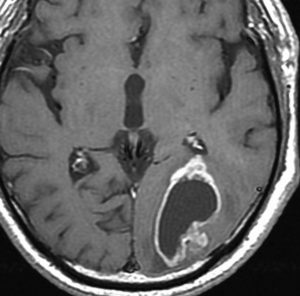

高齢者に発生したグリオーマです。左はガドリニウム増強MRIといいます。腫瘍の周囲が白く縁取られるように見えます。でも,右側のT2強調画像では,白く滲む部分が周囲に広がっています。

グレード3(かつての退形成性星細胞腫)かグレード4(膠芽腫),おそらく膠芽腫と「予想」できる画像です。確実ではないのですが,この予想は治療計画の上で重要なものです。